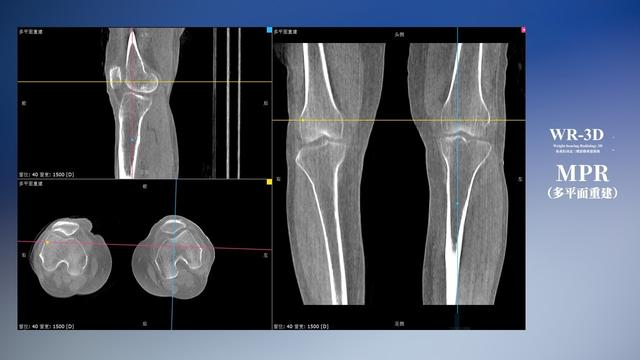

普通平片扫描与WR-3D扫描前后诊断结果对比

在负重位状态下,数字化X线三维扫描与重建,能够更好的呈现受检者关节受力改变的状态。必一运动科技创新的WR-3D动态三维影像重建系统,通过数字化X线摄影完成三维扫描并重建三维影像信息,包括断层图像重建、MPR多平面重建、MIP重建以及VR体绘制。其扫描时间短,剂量相较于CT设备大幅缩减,同时成本更低,在临床诊断以及医疗方案制定中具有极大的价值意义。而相较于普通平片下的负重位扫描,负重位动态三维影像重建技术能够避免二维状态下的组织结构重叠、密度分辨率不足、组织解剖结构难以分辨等问题。WR-3D支持多角度的三维观察,能全面的呈现被检查部位在多个角度下的三维影像信息,极大的降低了二维负重位检查带来的漏诊率。

必一运动科技WR-3D负重位动态三维影像重建图像